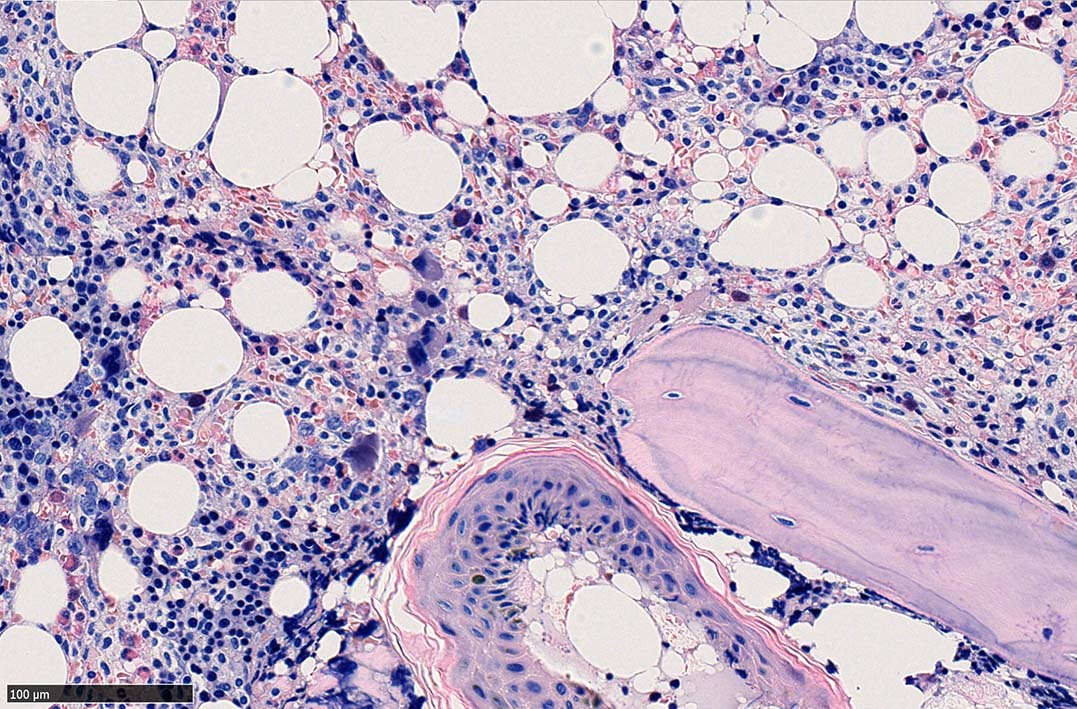

ASD-Giemsa陰性の細胞がシート状に増殖する. 核はクロマチン濃染, 核小体は不明瞭.類円形, 卵円形, くびれを持つ多稜形核, 長円形いびつで屈曲した核, など多彩. 細胞質は淡清色調, 広く淡明. 赤芽球血島は幼若赤芽球のみで形成される異形成像を示す. やや離れて成熟赤芽球が疎な集簇を示す.

Ag染色では, 疎な弾性線維が増生し,増殖細胞を小胞巣状に分画するいわゆる「lymphomatoid pattern」を呈する. 本例では, Mgkに異形成所見がある.

骨髄生検組織を使ったFCMのため, 細胞数が少数であるがCD19, CD20陽性のB-cellが優位で, lambda LC > kappa LCの偏倚がみられclonalな増殖が考えられる. B-cellはCD11c, CD25も発現している. Hairy cell leukaemiaが疑われる. CD103はこのFCMセットには組み込みがなかった.